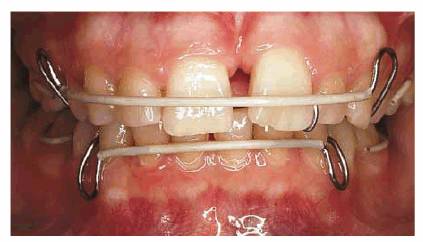

TREATMENT: A frenectomy was performed (see Figures 23-2C to

E). After

healing, maxillary and mandibular Hawley retainers were designed for the

patient (see Figure 23-2F). Note how a plastic coating that

conceals the labial wires permitted the patient to wear the appliance while

working. Therefore, she gained the advantage of wearing it more often. Figure 23-2F shows a maxillary appliance in

position and the amount of space needed to close the diastema. Figure 23-2G illustrates the result of wearing

the appliance for 18 hours per day for approximately 4 months. At this point,

the central incisors were mechanically bonded with composite resin to mask the

remaining interdental tissue space (see Figure 23-2H Figures 23-2I

and J show

how facial, mesial, and lingual surfaces were bonded to close the remaining

interdental spaces.

Figure 23-2F: After the tissue healed, removable Hawley appliances were placed. Note the tooth-colored Teflon tubing applied to the wire to mask the metal color.

Figure 23-2G: After approximately 4 months of wearing the appliance 18 hours per day, the teeth were together.